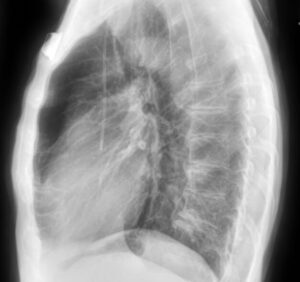

KA Imaging’s patented SpectralDR technology allows for clear differentiation between bone and soft tissue without motion artifacts, all within a single X-ray exposure. For example, in a chest X-ray, technicians can access an image of the lungs with the ribs subtracted. This greatly assists in diagnosis, removing obstructions (like bones) that can hide important medical information. Below is an example of three images produced with a single exposure using Reveal 35C. The example highlights a lateral view, not available with older dual-energy technologies:

bone image dual energy image spectraldr vs. bone suppression technology

Combining these enhanced capabilities with portability and minimal energy needs means this high-quality imaging can be available on demand, from resource-scarce areas of the world to space travel. Reveal 35C facilitates timely and accurate diagnosis, with proven results in pneumonia detection, lesion visibility, and use in the ICU.